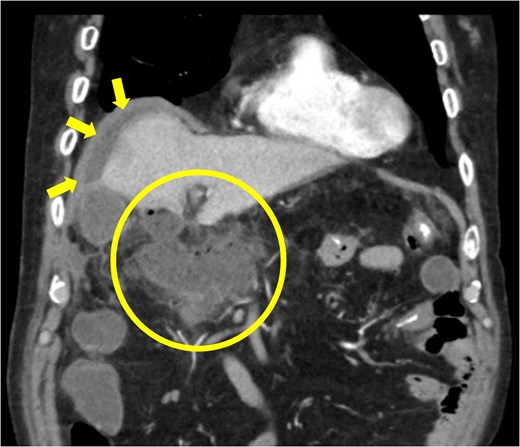

The amylase levels of drainage fluid and blood at postoperative day (POD) 1 (Ascites 6980 IU/dl, Serum 1123 IU/dl) and POD 3 (Ascites 673 IU/dl, Serum 487 IU/dl) revealed pancreatic fistula based on the criteria of International Study Group of Pancreatic Fistula [2]. After that, their results improved, and fluoroscopy showed no stenosis and leakage. Therefore, we removed all drains at POD 8, however the following day, the patient developed high fever. Plain CT revealed intraperitoneal fluid around subdiaphragmatic and duodenal stump (Fig. 3). We inserted a pig-tail drainage tube to the subdiaphragmatic space (Fig. 4). Since biliary fluid was discharged through the tube, we suspected duodenal leakage and started infusion of somatostatin analogs and antibiotics. At POD 13, the patient complained of whole abdominal pain with peritoneal signs. As the patient became hemodynamically unstable, we performed emergent laparotomy to lavage and insert multiple drainage tubes. Two perforation pinholes were identified in the anterior wall of the duodenum, near the stump. We resected the vulnerable duodenal stump including the perforation site and closed by Gambee’s method with unabsorbable 4–0 proline (Fig. 5). We inserted multiple drainage tubes (Fig. 6a): a C-tube from the cystic duct into the common bile duct to separate biliary juice and pancreatic juice, a dual drainage tube around the duodenal stump with continuous suction (Fig. 6b), a simple intraluminal drainage tube via the duodenum near the stump through a new skin incision on the left side of the abdomen for duodenal decompression, and a drainage tube into the rectovesical pouch. After the reoperation, we irrigated the cavity around the duodenal stump through each drain with saline. Since the contrast agent did not flow into the duodenum and the cavity around the duodenal stump gradually got smaller (Fig. 7), oral intake of fluid diet was initiated at POD 37. However, fistulography at POD 44 showed that the fistula of duodenal stump had relapsed (Fig. 8). Although we considered performing second reoperation for duodenal stump closure, due to the cavity around the duodenal stump was located, we continued conservative management and irrigation via drainage tubes. Fistulography demonstrated no leakage from the duodenal stump at POD 56, and the patient discharged at POD 59.

Diagnosis of postoperative duodenal perforation. CT showed ascites in subdiaphragmatic space (arrow) and around duodenal stump (circle) at POD 8.

Primary drainage for duodenal fistula. As percutaneous approach, we inserted a pig-tail drainage tube to subdiaphragmatic space (asterisk) using X-ray fluoroscopy.